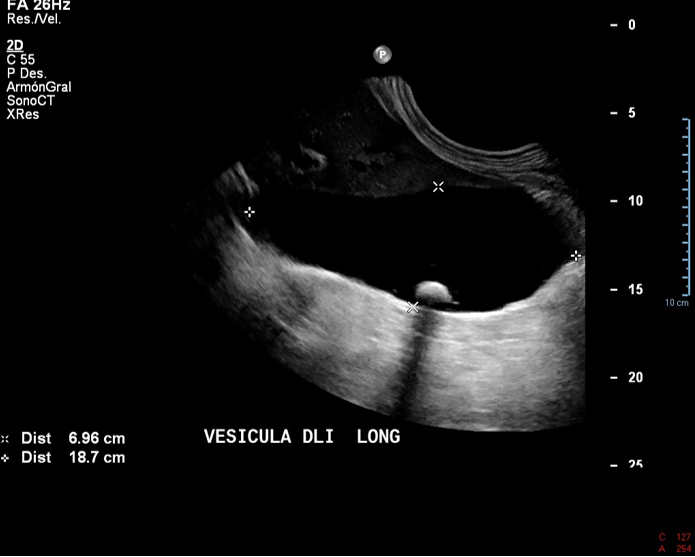

• Vesícula ampliamente distendida (hidrops), presenta barro biliar y calculo móviles. Colelitiasis asociada a barro biliar, sin signos de impactación. Wirsung de calibre conservado.

Vesícula biliar sobre distendida, mide 18,8 x 7 cm en sus ejes mayores. Presenta paredes finas con bilis ecogénica y cálculos móviles en su lumen, el de mayor tamaño, mide 21 mm. No hay Murphy ecográfico.